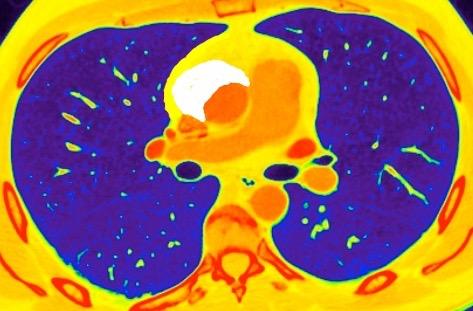

131. ESPACIO SUBCARINAL. OCUPACIÓN

Densidad baja uniforme del espacio. Pared interna de BPI-BI visible.

BPI sin alteraciones Ángulo carinal normal

Crecimiento AI

Ganglios Quiste broncogénico

Ganglios subcarinalesl Ángulo carinal normal